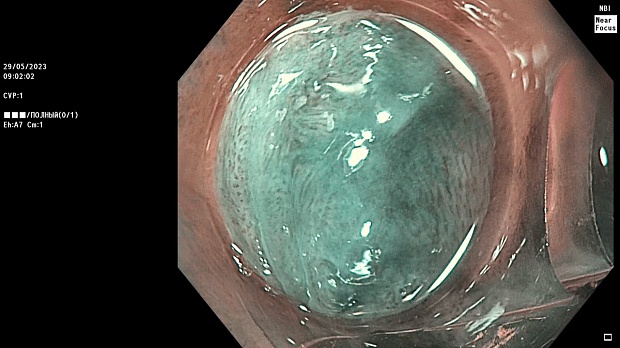

Иллюстрация №2: Эндофото. Сидероз нижней трети пищевода, осмотр в белом свете в близкофокусном режиме

Согласно полученным данным - в среднегрудном и нижнегрудном отделах пищевода определялась проксимальная граница плоских неправильной формы поверхностных рубцов суммарной протяженностью до 8,0 см. На этом фоне в зонах поверхностных рубцов по задней полуокружности визуализировались участки гиперпигментации в темный цвет (Рис. 1). При исследовании в режиме Dual Focus было отмечено наличие мелких (до 0,001 см) черно-коричневых включений, расположенных субэпителиально - в строме слизистой оболочки, сливания их в единый конгломерат не определялось (Рис. 2). При эндосонографии с применением минидатчика с частотой сканирования 20МГц выявлено, что все слои стенки четко дифференцируются, не утолщены, в слизистой оболочки визуализированы мелких гиперэхогенные включения с эхотенями (Рис. 3).